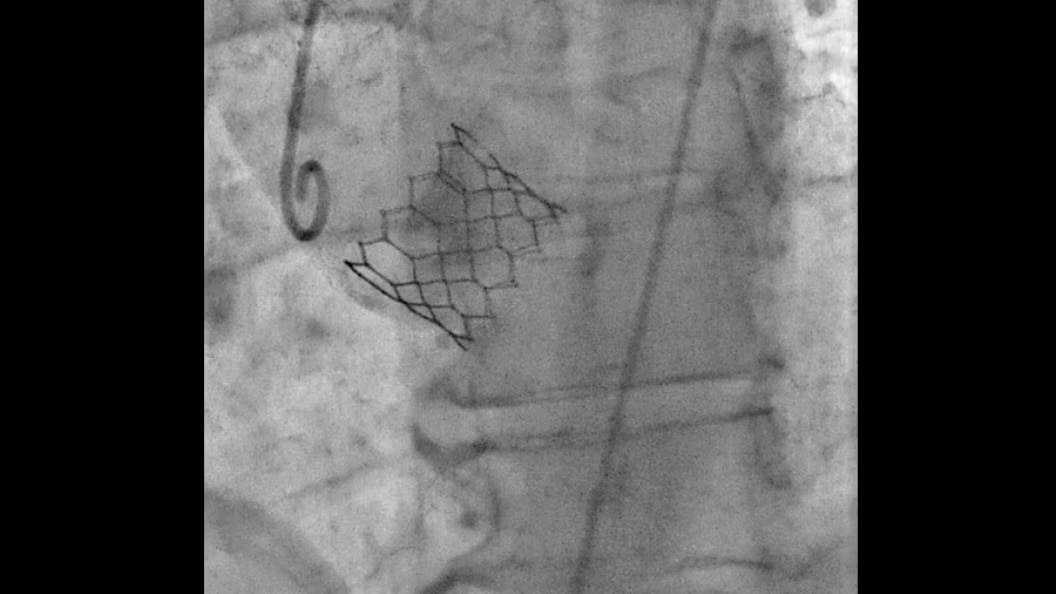

evar-assist-2-tile-en

EVAR ASSIST

Perform endograft procedures in one go with intuitive tools and a simplified workflow - less radiation, more efficiency